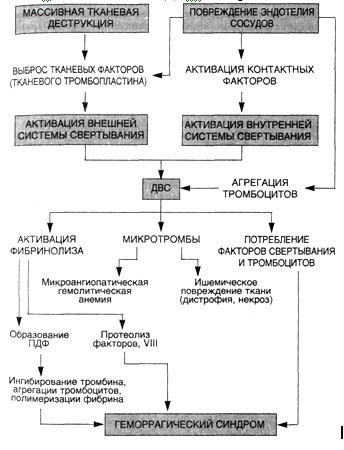

По ней, жировая эмболия – это вообще часть единой системы свёртывания крови, называемой посттравматической дислипидемической коагулопатией, о которой мы, пока, естественно, ничего не знаем. Знаем только, что в образовании жировых глобул как-то участвуют тромбоциты (элементы крови отвечающие за свёртывание крови), на начальном этапе их появления. А значит можно вроде как рассматривать ЖЭ как частный случай нарушения свёртываемости при травмах (это когда в результате сильных повреждений система свёртывания крови сходит с ума и начинает создавать тромбы прямо в кровеносном русле. Данное состояние называется синдромом диссеминированного внутрисосудистого свёртывания. Это вообще шляпа-шляпная, крест-крест, череп, гроб, смертЪ).